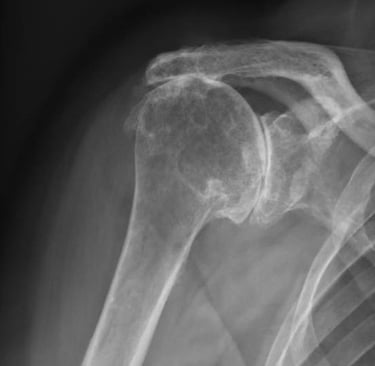

Vous présentez une arthrose de l'épaule / gléno-humérale ; avec une coiffe des rotateurs parfaitement compétente.

Vous présentez une arthrose de l'épaule / gléno-humérale ; ET une coiffe des rotateurs détériorée (1)

La conséquence est une omarthrose / usure excentrée de l'épaule ( 2).